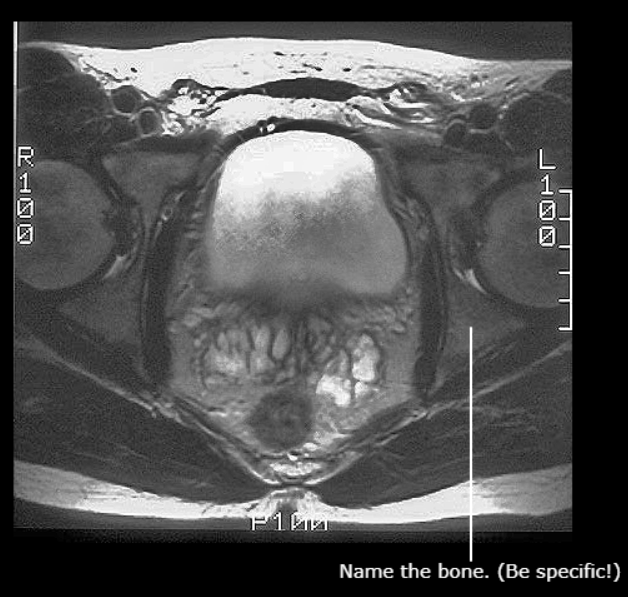

(Just name the bone, not that specific gap)

Sacrum

Ischiopubic Ramus

Pubis